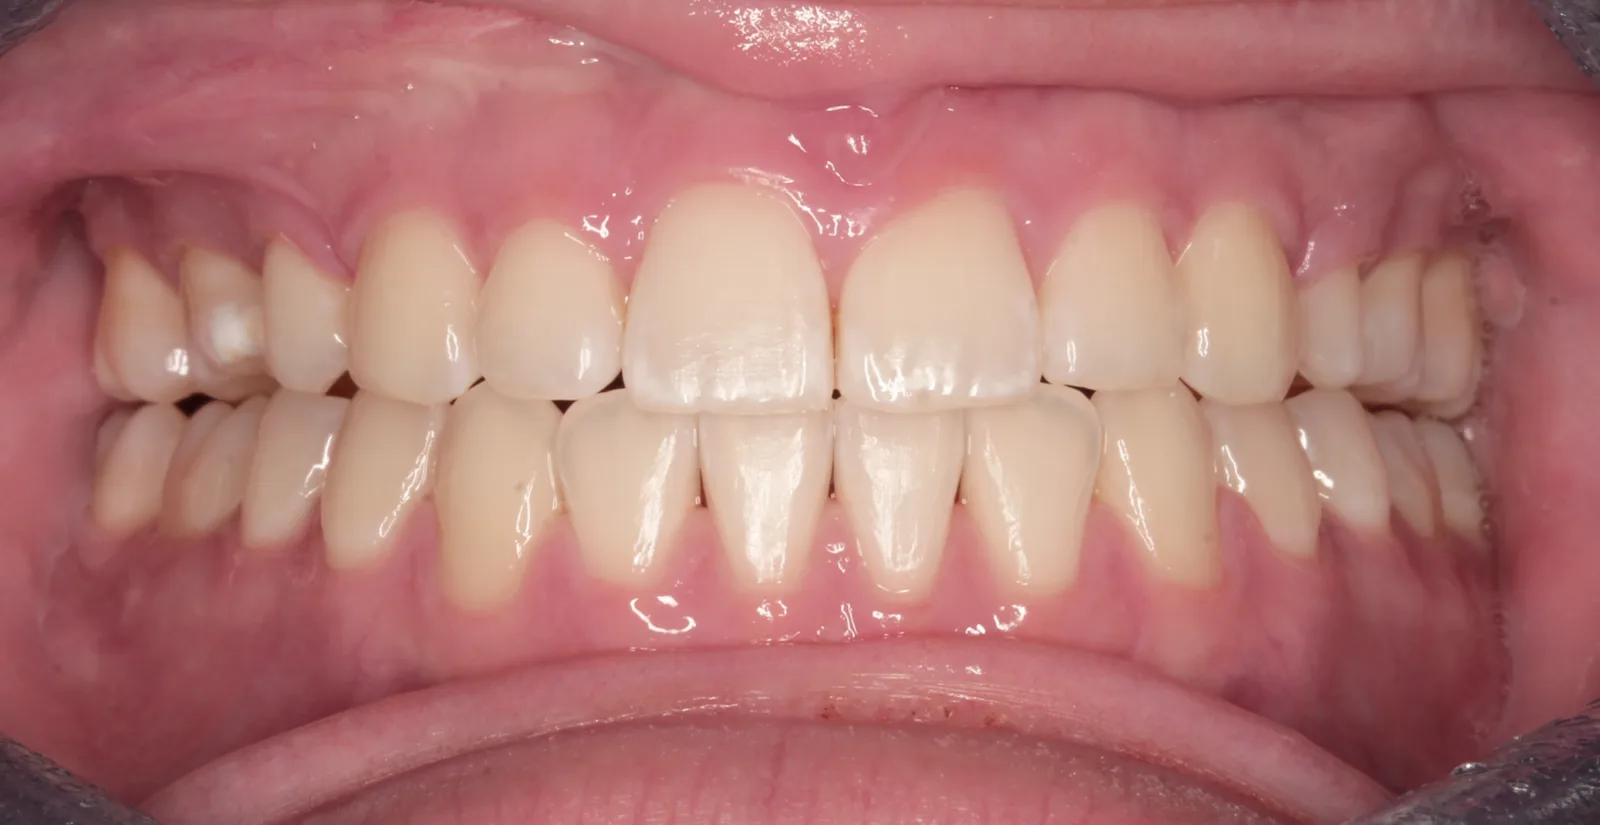

After teeth alignment comparison: Intraoral after photo of Metal Self-Ligating Braces & Orthognathic Surgery showing this transformation was designed with intention. After

This transformation was designed with intention. Dr. Benson used braces to sculpt alignment and prepare the bite, then collaborated with an oral surgeon to reposition the mandible through orthognathic surgery. The result: a stable bite, restored facial balance, and symmetry achieved.